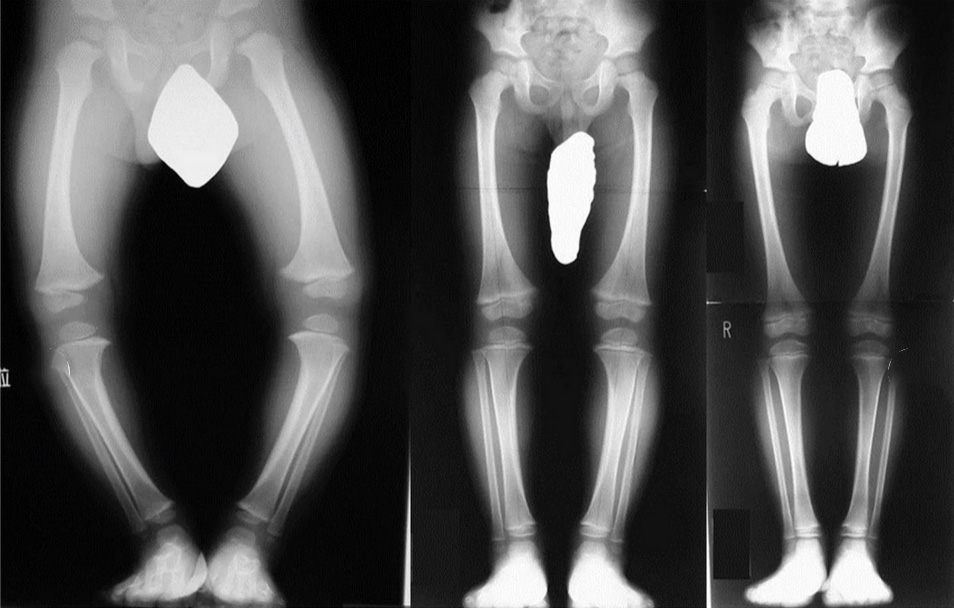

写真の様に脚が大きく曲がり、アルファベットの“O”のように見えることから、О脚と呼ばれています。

О脚は乳幼児(0~6歳くらい)の足の変形で多く見られます。原因には以下のものが考えられます。

●成長と共にО脚が治っている(生理的О脚)

このように歩きはじめの赤ちゃんの脚はО脚であることが多く、そのほとんどが自然に治ります。